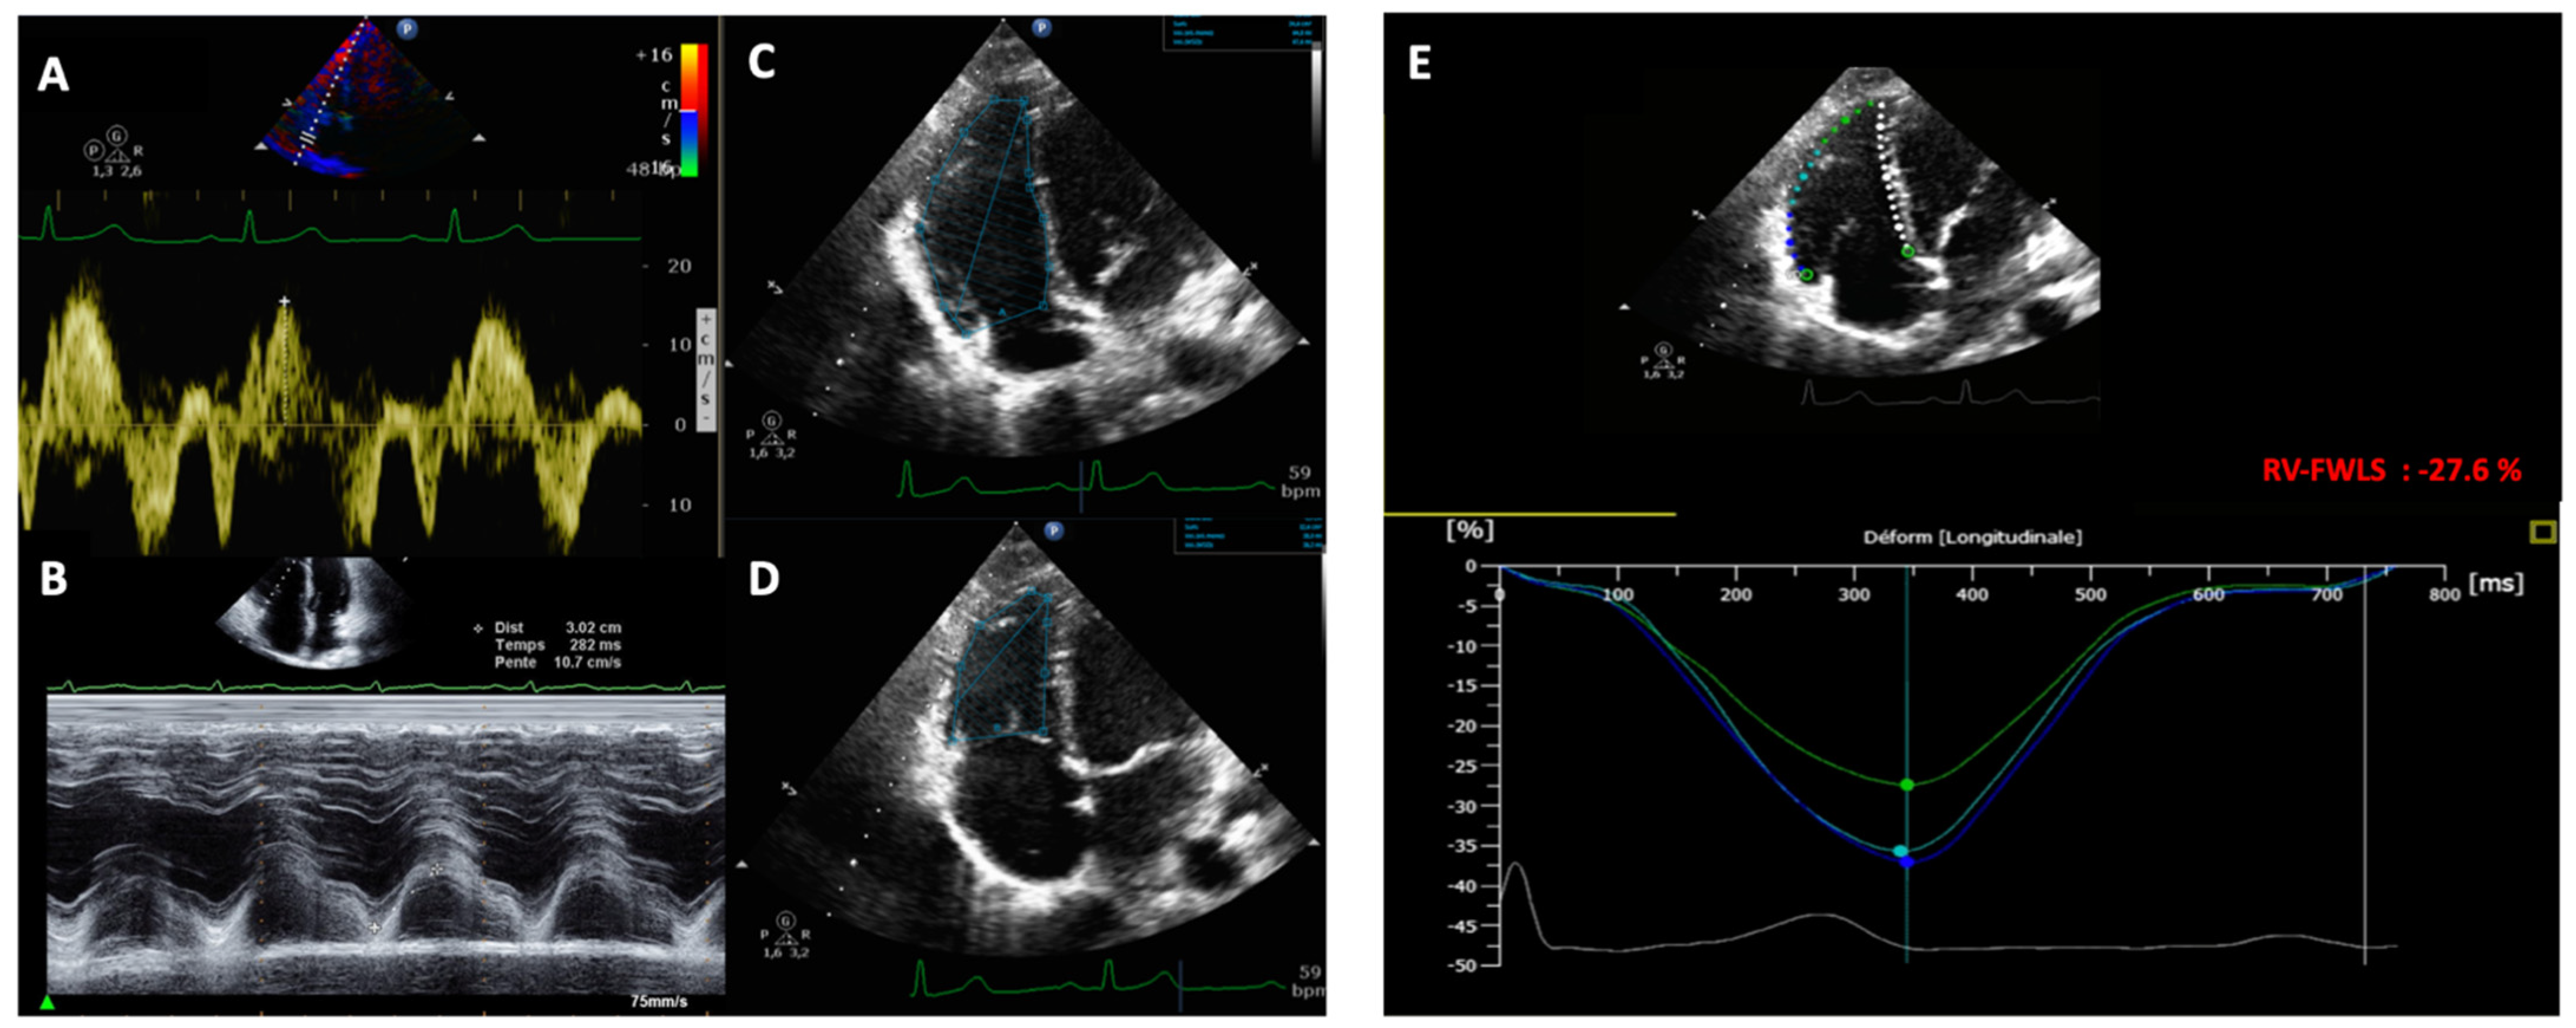

RV systolic function: RV conventionnal and 2D-strain parameters are summarized in Figure 1. We measured conventional RV parameters (TAPSE, RV-S’, and RV-FAC) according to international guidelines [18]: the RV-S’ wave was measured in the apical four-chamber view using Doppler tissue imaging mode (Figure 1A). TAPSE was measured using M-mode with a cursor placed at the junction of the lateral tricuspid leaflet and the RV-free wall (see Figure 1B). RV systolic and diastolic areas were measured in the apical four-chamber view in 2D mode. RV-FAC was calculated by subtracting the end-systolic area from the end-diastolic area and dividing this value by the end-diastolic area (see Figure 1C,D).

Figure 1. Measurement of the RV conventional parameters and the RV-FWLS in a RV-focused apical four-chamber view. (A) RV-S’ wave measured in tissular Doppler imaging. (B) TAPSE measure in M-mode. (C,D) End-diastolic RV area and end-systolic RV area measured for RV-FAC. (E) Automatic RV-FWLS measured by the QLAB AutoStrain Software.

RV 2D-strain analysis: RV-FWLS was obtained using 2D AutoStrain software (AutoStrain, QLAB version 15, Philips Medical Systems, Andover, MA, USA) in an RV-focused four-chamber view at 50 to 70 frames/s. Fully automated RV-FWLS were measured by the software. We performed manual editing to fit RV myocardial wall thickness. The RV-FWLS was automatically calculated as the average of the three segments (basal, mid, and apical) of the RV-free wall (Figure 1E). The longitudinal strain was defined as the percentage of myocardial shortening relative to the original length and presented as a negative value, with a larger negative strain value reflecting better shortening. We used the absolute value of RV-FWLS for sampler interpretation.